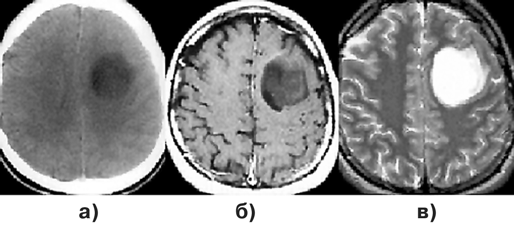

Для доброкачественных диффузных астроцитом при КТ наиболее характерна зона понижения плотности, не имеющая четких границ с окружающим мозговым веществом (рис. 1а, г). Внутривенное введение контрастного вещества обычно не приводит к повышению рентгеновской плотности очага. Разрешающая способность КТ недостаточна для идентификации границ опухоли, особенно изоплотностной по отношению к мозговому веществу.

МРТ — более точный метод визуализации астроцитом. Доброкачественные астроцитомы представляются изо— или гипоинтенсивными на Т1-взвешенных изображениях (рис. 1б, д). В режиме Т2, наиболее информативном при данной патологии, эти опухоли могут выглядеть как сравнительно хорошо отграниченная зона гомогенно повышенного сигнала (рис. 1в, е). “Масс-эффект” выражен, как правило, незначительно, контраст накапливается редко. Так как эти опухоли обычно диагностируются только на стадии выраженных клинических проявлений, для них типично поражение одновременно нескольких долей мозга. Перифокальный отек не характерен.

Рисунок 1. Астроцитомы:

а — астроцитома левой заднелобной области (КТ с контрастным усилением); б — астроцитома левой заднелобной области (МРТ, Т1-взвешенные изображения); в — астроцитома левой заднелобной области (МРТ, Т2-взвешенные изображения); г — фибриллярная астроцитома правой лобно-височной области (КТ с контрастным усилением); д — фибриллярная астроцитома правой лобно-височной области (МРТ, Т1-взвешенные изображения); е — фибриллярная астроцитома правой лобно-височной области (МРТ, Т2-взвешенные изображения)